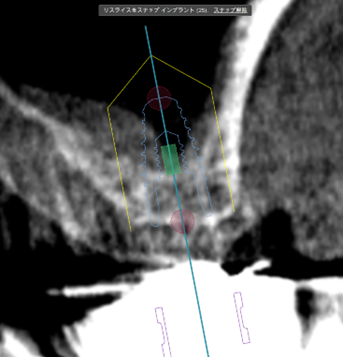

③ガイデッドサージェリーにてインプラント埋入しました。

④計画通りの埋入が出来ました。